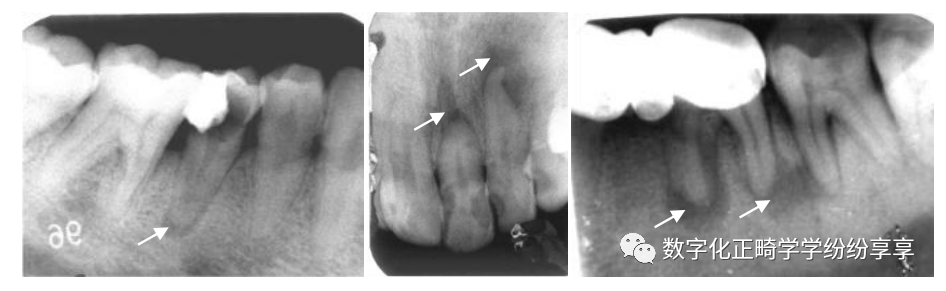

牙发育异常 Dental anomalies:

畸形中央尖 曲面断层片怎么看正畸【曲面断层片(全景片)】如何解读和查看:牙周?牙体?牙髓?关节?_https://www.jmylbn.com_新闻资讯_第16张

牙内陷

①右上 2 畸形舌侧尖(伴阻生牙);②左上 2 畸形舌侧窝;③右上 2 牙中牙

融合牙

分别为右下 1、2 的完全性融合和不完全性(牙冠)融合

阻生牙

拍片注意:阻生牙位臵、方向、本身情况、与邻牙关系、数目及形态、与下牙槽神经管距离和磨牙后间隙大小等。